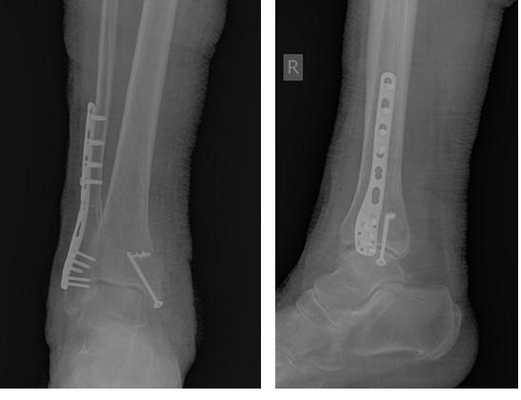

На контрольных рентгенограммах после операции положение отломков, металлофиксаторов правильное, подвывих таранной кости устранён.

Пациентка выписана на 2 сутки после операции на амбулаторное долечивание.